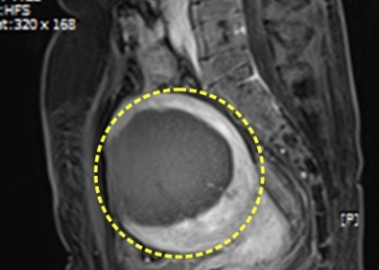

다발성 자궁근종 치료 사례